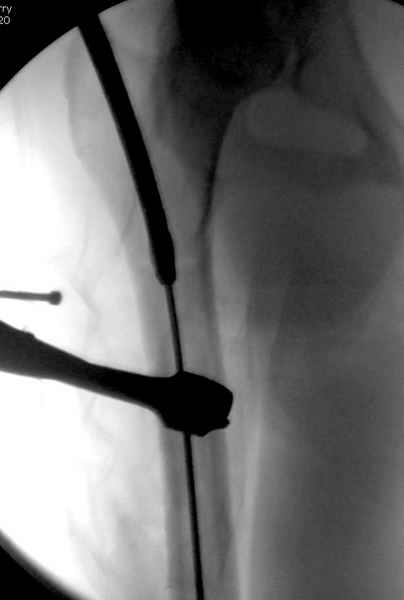

Второй случай тоже репозиция из малого доступа, больному 19 лет, множественные огнестрельные повреждениия конечностей, живота и черепа, правая конечность холодная, без пульсации. Ортопедический диагноз: огнестрельный перелом правого бедра. При срочной ангиографии повреждения сосудов не подтвердилось, конечность из-за ургентности состояния больного зафиксирована временным наружным фиксатором и больной оставлен на операционном столе для срочной лапаротомии хирургической службой.

Больной долго оставался нестабильным, только на 14 день удалось заменить на антеградный интромедуллярный штифт TFN (trochanteric femoral nail) SmithNephew. После неудачной попытки закрытой репозиции, несмотря на использование "joystick", проксимальный стержень от

наружного фиксатора, (перелом начал срастаться) репозицию провели из малого доступа, затем остальные этапы операции.